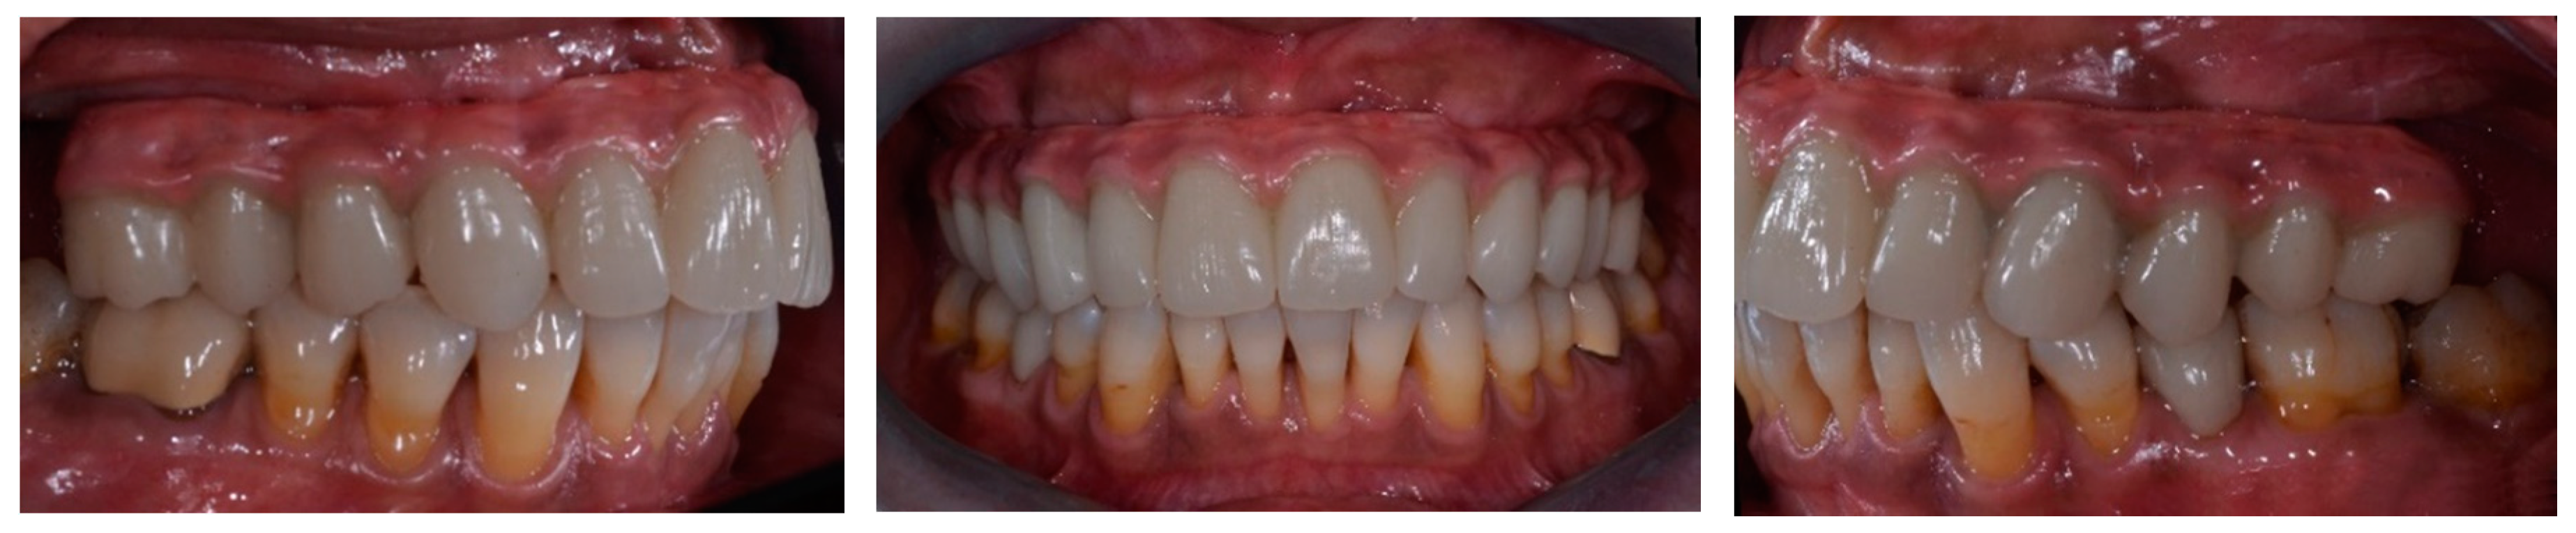

2. Materials and Methods

2.5. Prosthetic Protocol

3. Results